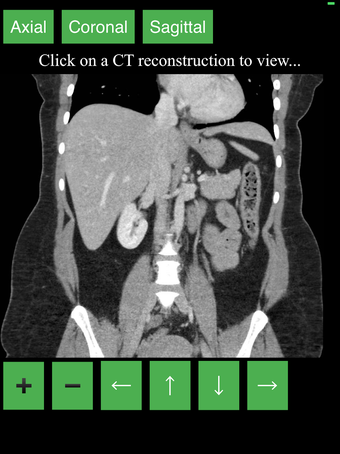

هذا تطبيق فريد من نوعه، تم تطويره من قبل مجموعتنا، لغرض توفير طريقة بسيطة ومفيدة لتعلم تشريح الجسم بالمقطع العرضي.

نقدم أفضل طريقة لتعلم هذا الموضوع، باستخدام جهاز تصوير تشخيصي (CT). نحن نحاول جعل عملية التعلم سهلة وممتعة قدر الإمكان، باستخدام نموذج ثلاثي الأبعاد للجسم البشري.

ما هو CT؟

هذا نوع من التصوير الذي يستخدم أشعة الأشعة السينية لعرض داخل الجسم وبناء صورة للأعضاء والعظام. هذا مفيد للكشف عن الأمراض والإصابات، وأيضًا لمساعدة في فهم تشريح الجسم.